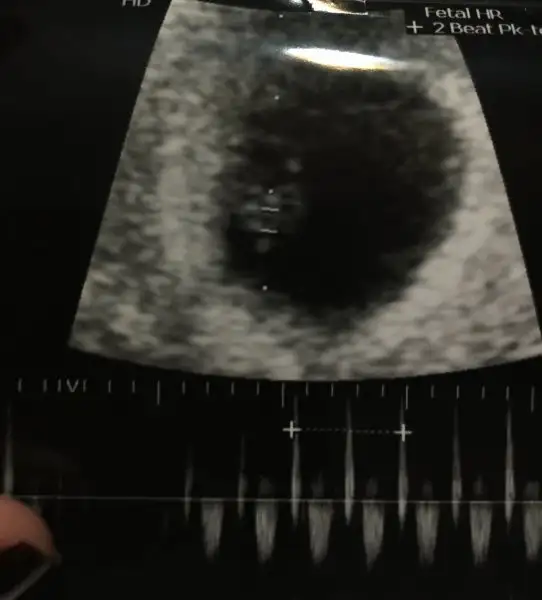

Havalianne__ Havalianne__ rica etsem benim fotoğraflarada bakarmısın ilki alttan 5.hafta diğerleri karından 7. Haftada çekildi merakdan ölüyorum içime sürekli kız diye doğuyor ama kısmet Allah bilir tabii:KK49: